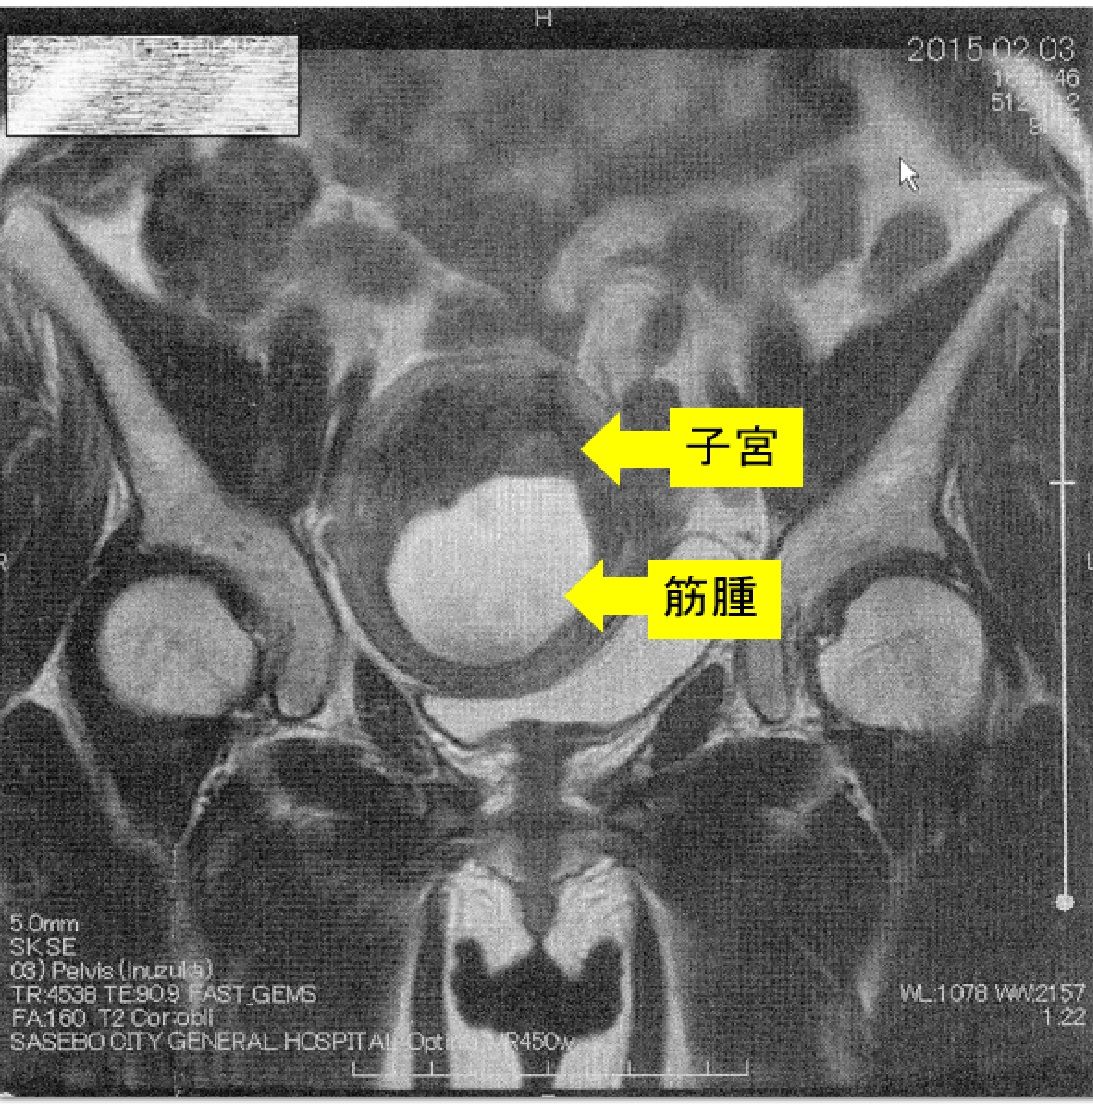

¡Ú2015ǯ2·î3Æü¡¡£Í£Ò£É¼Ì¿¿¡Û

¢¨Çò¤¤Éôʬ¤¬¶Ú¼ð¡¢¼þ¤ê¤ÎÉôʬ¤¬»ÒµÜ¤Ç¤¹¡£